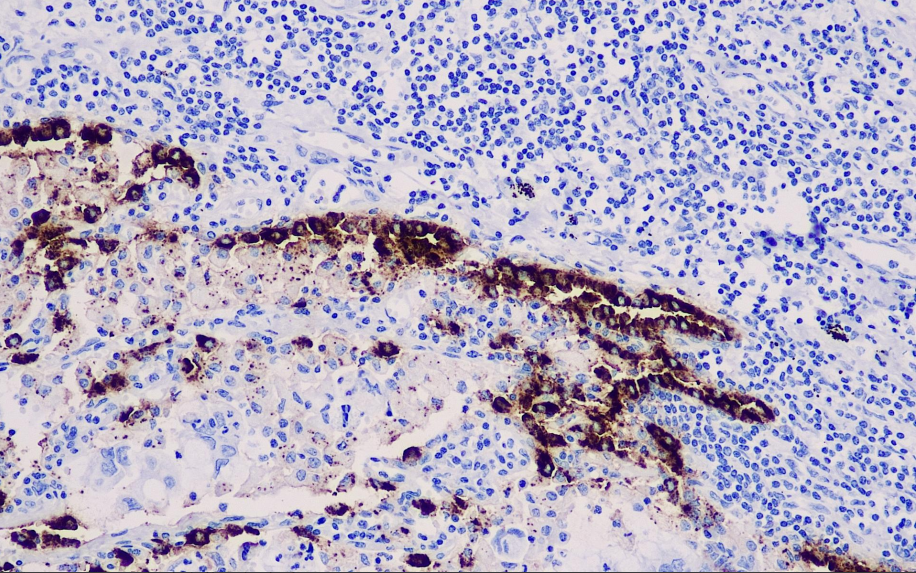

Cell localization: Cytoplasm

Positive control: Lung

The SP-B precursor undergoes glycosylation in the Golgi apparatus and is hydrolyzed at the C- and N-termini by cathepsin D-like enzymes. Pulmonary surfactant is a complex composed of phospholipids and proteins secreted by type II alveolar cells. It reduces surface tension at the alveolar-liquid interface and provides the normal airflow necessary for alveolar stability. Four proteins, A, B, C, and D, have been isolated from the pulmonary surfactant protein complex. SP-A (28–36 kDa) and SP-D (43 kDa) are collagen-glycoprotein-binding proteins, while SP-B (8–9 kDa) and SP-C (4 kDa) are non-collagenous hydrophobic proteins. SP-B is stably expressed in the acini, papillary projections, and bronchioloalveolar regions of lung adenocarcinoma. It is not expressed in lung squamous cell carcinoma, large cell lung carcinoma, or non-adenocarcinoma lung cancers. Therefore, this antibody is meaningful in the study of lung adenocarcinoma.

SP-B antibody reagents can specifically bind to SP-B molecular antigens. Immunohistochemistry kits containing SP-B antibody reagents are suitable for the auxiliary diagnosis of lung adenocarcinoma.